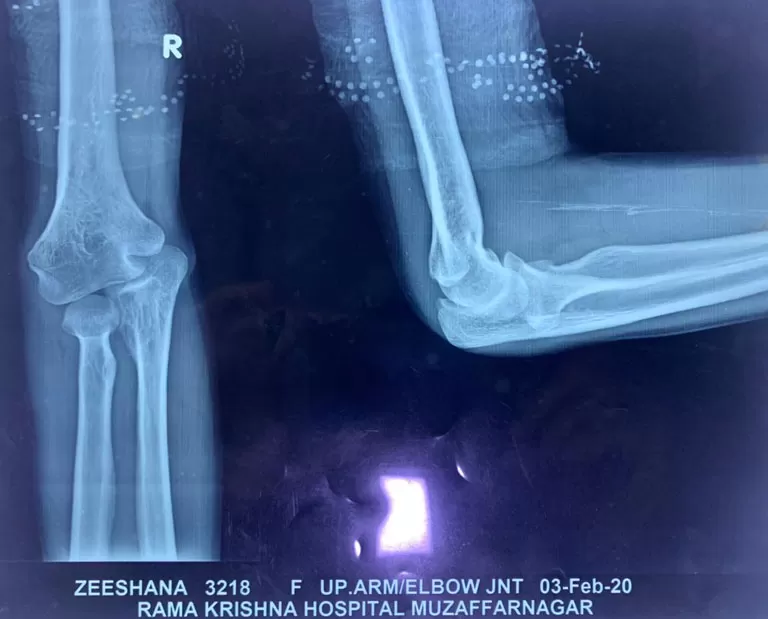

Mrs. Zeeshana

Name: Mrs. Zeeshana

Date of Operation: 03 Feb 2020

Age: 33 Years